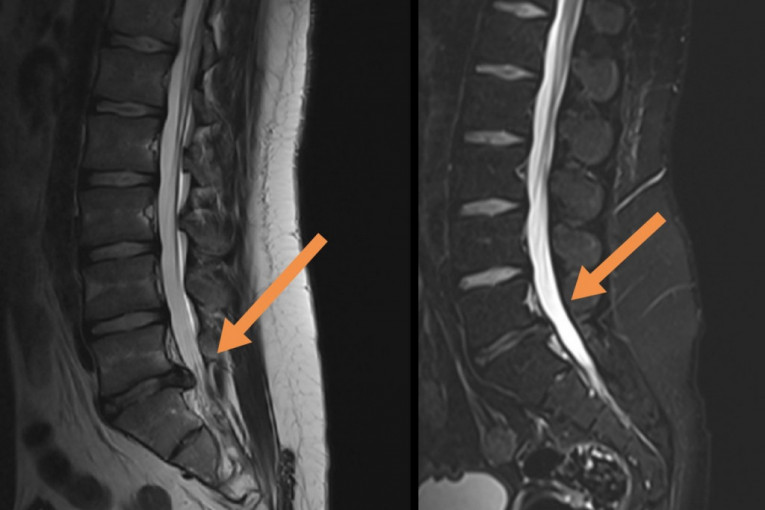

Foto: Privatna arhivaNajčešći problem bolnih leđa je diskus hernija koja se obično javlja između 30 i 50 godine života. Razlog za ovo jeste što prirodni proces starenja kičmenih diskova počinje već u detinjstvu i ranoj mladosti, tako da nije neobično da bolest nastane i kod osobe od dvadesetak godina. Simptomi zavise od nivoa u kom se javio problem. Najčešće se javlja u nivou L5/S1, tada bol ide duž čitave noge sve do stopala, obično je prisutan i bol u listu uz jak spazam mišića,a može doći i do pada stopala, kao i oštećenja sfinktera ( učestalo mokrenje, nemogućnost mokrenja, erektilna disfunkcija). Vrlo često se dešava da pacijenti lutaju u traženju dijagnoze, dešava se da idu kod urologa, nefrologa, ili gastroenterologa misleci da je problem te prirode. Kad je vrat u pitanju, obično stradaju C4/C5/ i C6.

Dekompresijski tretman kičme ili DTK je jedini neoperativni tretman, kompjuterski kontrolisan i dijagnostički povezan, koji postiže odlične rezultate kod teških slučajeva diskus hernije, degenerativnih promena, artritisa, stenoze spinalnog kanala i pritiska na nervne korenove. Dekompresiona terapija kicme deluje tako da putem cikličnih faza distrakcije i relaksacije i pravilnom pozicioniranjem diska dovodi do povećanja međupršljenskog prostora za nekoliko milimetara (1-2), oslobađa živce - između njih, smanjuje bol, trnjenje, glavobolje, vrtoglavice, kao i slabosti u šakama i stopalima. Ovaj tretman stvara negativan pritisak i efekat vakuma u samom diskusu koji se nalazi izmedju dva pršljena i na taj način povlači herniju unutar diska. Vakum povećava cirkulaciju oko diska i tako leči upalni proces. Dekompresijski tretman vrši istezanje receptora u mišićima i ligamentima oko kičmenog stuba, smanjuje pritisak na medjupršljenske zglobove povećavajući pokretljivost kičme.